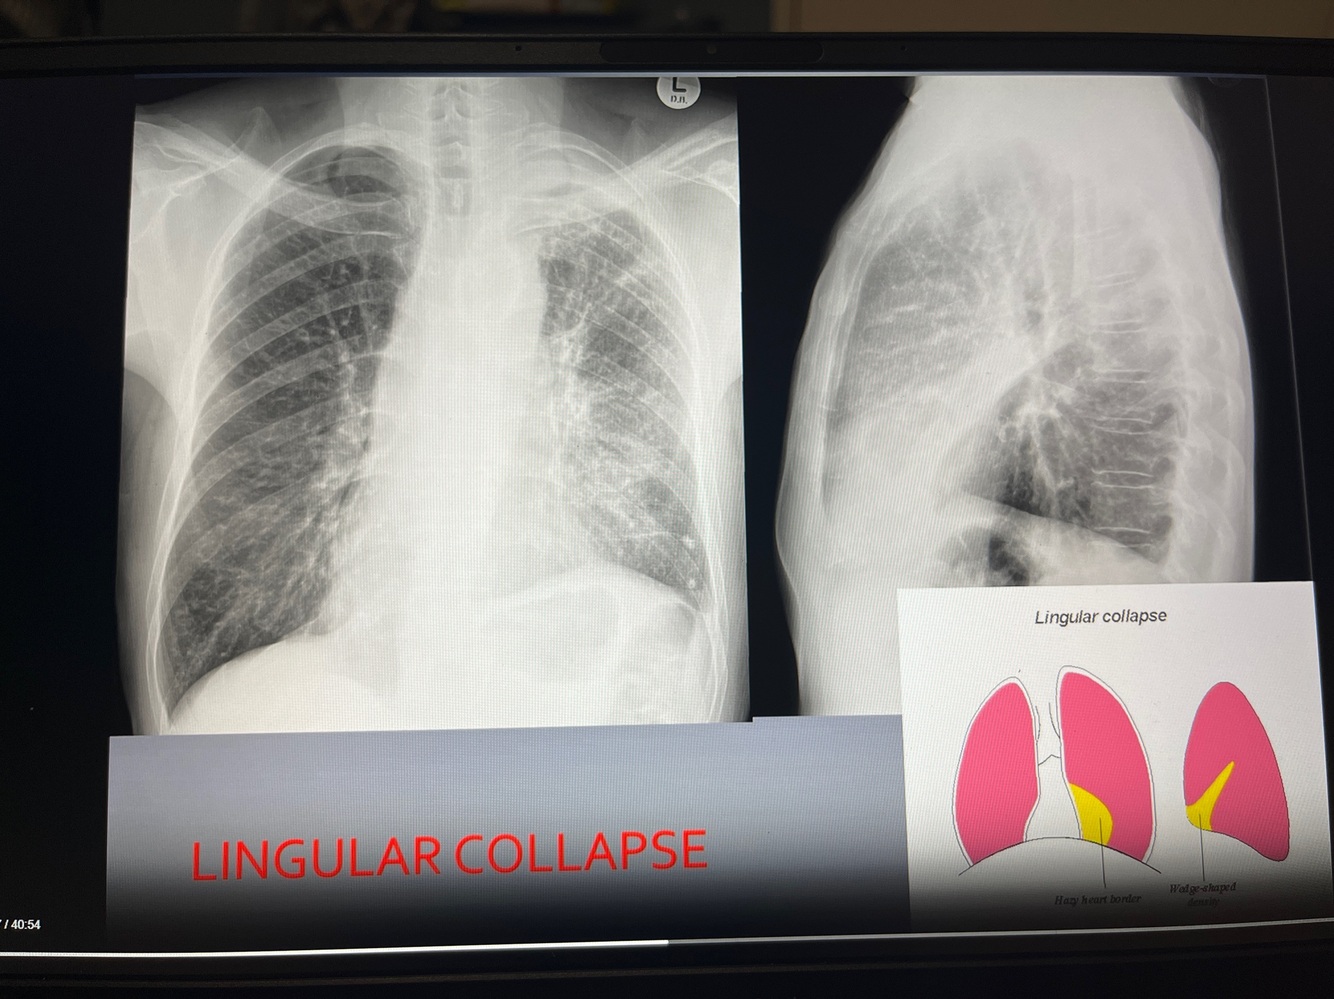

A

Lingular collpase